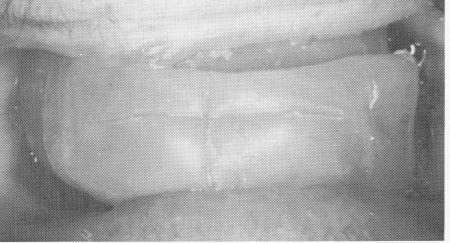

Fig. 15-7, A, The fixed denture is cemented with oxyphosphate of zinc cement. B, The incisal edges of the mandibular restoration were parallel to a horizontal plane, fabricated completely independently of the upper denture.

1 Incisal edge of lower implant prosthesis parallel to horizontal plane